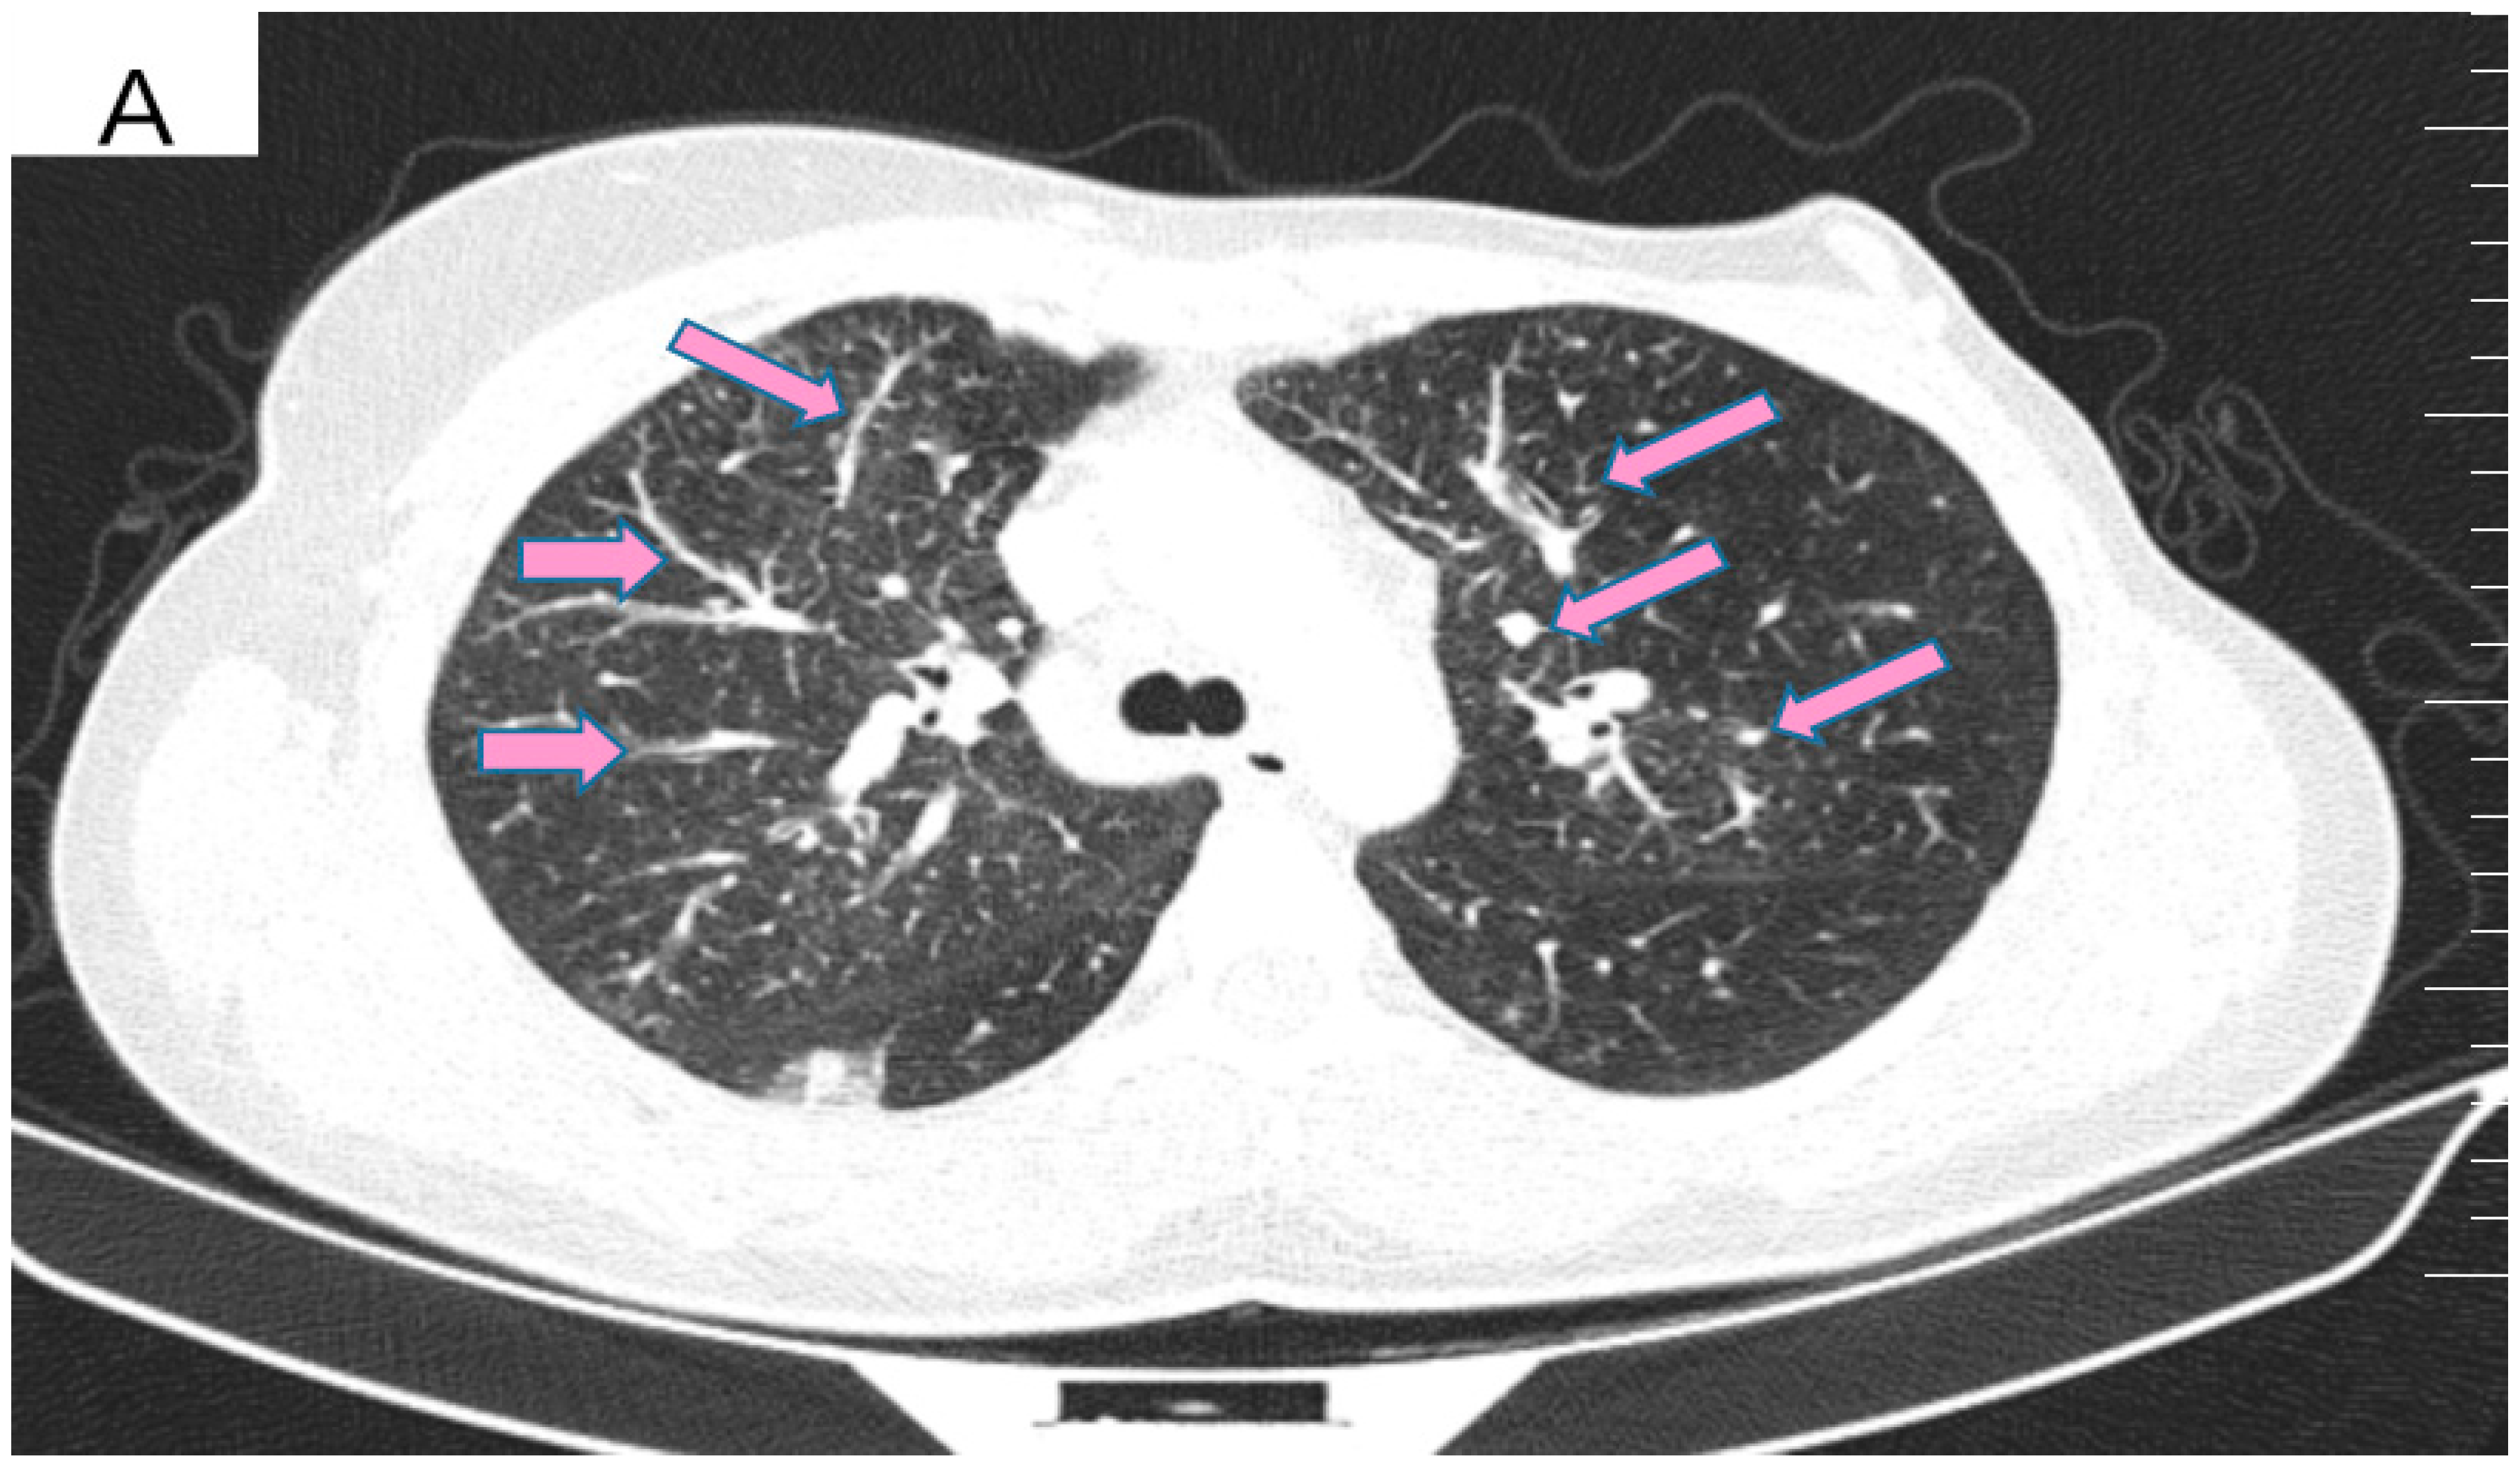

However, 2 years after the initial diagnosis, in February 2021, during the clinical and biological evaluation for an expander replacement, lab reports highlighted abnormal values of the liver enzymes—aspartate aminotransferase (AST) 155 UI/L and alanine aminotransferase (ALT) 114 UI/L. After excluding an infectious or toxic etiology, an abdominal ultrasound revealed the presence of hepatic metastases in the eighth hepatic segment. An abdominal MRI was immediately requested which showed a liver tumor mass of approximately 9.6/6.6 cm with the aspect of liver metastasis (Figure 3A). Subsequently, chest CT revealed carcinomatous lymphangitis (Figure 4A) and millimeter areas of osteolysis in the T1 and L1 vertebral bodies and the sternal body, without brain metastases on cerebral CT. During workup period, the patient’s clinical status worsened by developing symptoms of respiratory failure with dyspnoea at minimal exertion with oxygen saturation (SaO2) of 75% and rapid progressive dry cough. Furthermore, the liver was palpable 6 cm below the costal rim. Hepatic assays were exacerbated by a severe increase in AST 635 UI/L and ALT 309 UI/L (Figure 5), but with normal value of total bilirubin 1.14 mg/dL, alkaline phosphatase 179 U/L and gamma-glutamyl transferase 154 U/L with slightly increased values, albumin 3.01 g/dL, International Normalized Ratio (INR) 1.2. Tumor marker CA 15-3 was also increased (286 U/mL). At that time, the prognosis was extremely reserved.

Figure 4.

(A) Pretreatment CT scan of the lungs showing interlobular septal thickening and multiple bilateral peribronchovascular nodular opacities. (B) CT scan showing resolution of interlobular septal thickening and remission of most of the pulmonary nodules after treatment with six cycles of Pertuzumab, Trastuzumab and Paclitaxel.